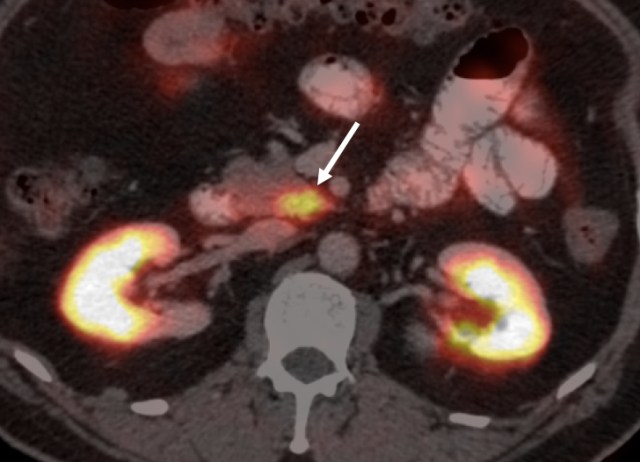

For example, a distant relative of mine, a 50-year old gentleman, recently underwent an upper GI scopy for symptoms of gastritis. The scopy found a small duodenal nodule, which came out to be a well-differentiated neuroendocrine tumor (grade I NET with MIB1 index of <1%) on biopsy. This was felt to be an incidental finding (these are leave alone lesions). However, a somatostatin scan was performed to confirm that this was localized disease. Here is the final impression given in the report.

The radiologist describes that known primary duodenal nodule does not show somatostatin uptake. However, there is mild uptake described in a portocaval node, and then the radiologist adds the ‘query’, labeling it ‘?metastatic’. Most of us will find it a very reasonable description, but pause and think from the patient or the referring doctor point of view. If the node is not metastatic, the patient does not require any treatment or even surveillance. However, if it is metastatic, he will require a Whipple’s surgery, with a 3-5% risk of death and a 25-30% risk of morbidity! And the radiologist has not given any differentials, nor stated what s/he feels actually about the node. Query by its definition indicates uncertainty rather than certainty, and whether there is a 50-60% chance of the node being metastatic vs a 70-80% chance vs a 20-30% chance makes a big difference. The single ‘?metastatic’ is a very incomplete description indeed!

A better worded impression (particularly considering that the pre-test probability of it being metastatic is very low) could have been ‘there is mild uptake in a single portocaval node, which may be physiologic and benign, although metastasis remains in the differential’. Luckily, the relative shared the scan with me and our nuclear medicine dept quite categorically stated that the purported nodal uptake was actually physiologic uptake in the uncinate process of the pancreas. The ecstatic patient was supremely thankful, and is leading a normal and healthy life since then.